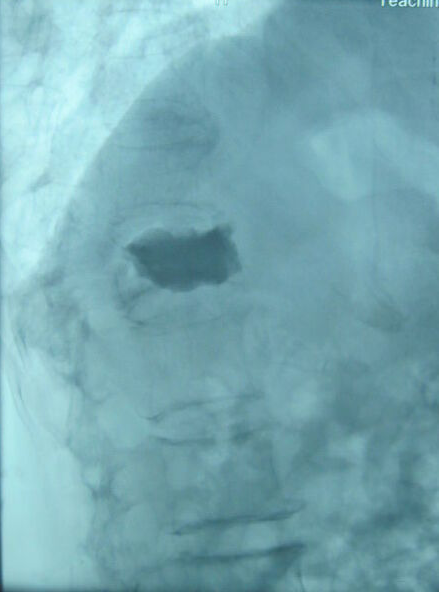

女性,81岁,腰背部剧烈疼痛1月,翻身、下床困难,保守治疗及卧床休息无效。无明显外伤史史。术前CT、MRI显示胸12椎体新鲜压缩骨折。行经皮椎体成形术治疗,注入骨水泥。术后疼痛明显缓解,能够轻松地翻身、下床、坐立。

针尖位置满意后,注入骨水泥。图中黑色部分代表骨水泥。骨水泥填在椎体里面,支撑起椎体,将骨折碎片粘在一起,就能明显减轻疼痛。当然要准确判断到底是哪一个椎体出了问题。